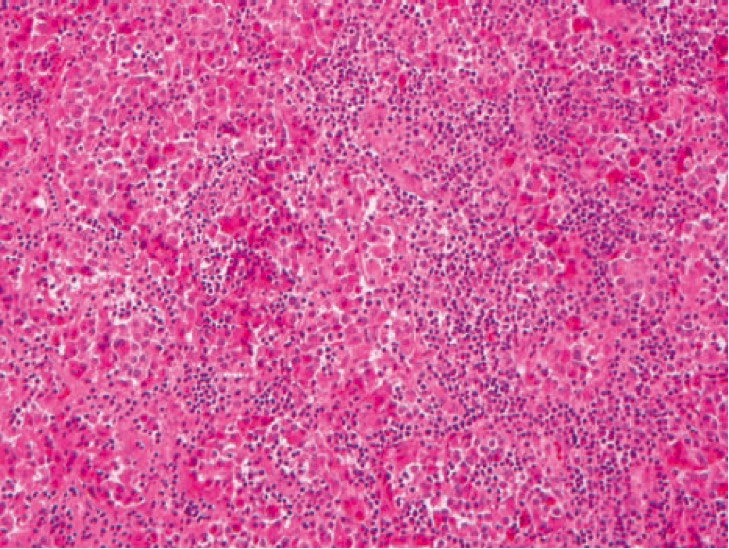

1066. 32-Летней недавно родившей пациентке выполнили биопсию гипофиза вследствие симптомов его недостаточности

диагноз